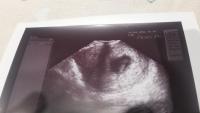

@littlebiscuit:Nagyon szuper!!!

Annyira boldog vagyok én is

Szuper, hogy feltöltötted

<3 Kellemes gyönyörködést

és boldog babóvárást!!!! <3